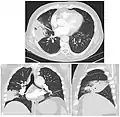

Chest radiograph of a lobar pneumonia, affecting the right middle lobe.

CT scan of the same case.